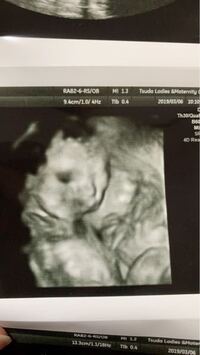

エコー写真の横顔 唇が出過ぎ 36週目です。この週数にしてはよく映ってる!と言われて横顔がはっきり映った写真をくれました。 鼻と同じくらいの高さまで口が突き出ているのですが、それくらいは当然のことなのでしょうか? 検索をかけると同じようなことを言っている方が沢山います。 鼻が低いかどうかを次のチェックを行うことで判断することができます。 判断基準として試してみましょう。 ・横顔のeラインをチェックする 横顔を見た時に鼻の先端とあごの先端を結んだラインを「eライン」と呼びます。 つまり、 鼻の下から口のラインまでの長さが、顔の下半分の長さの3分の1程度が美人のバランス ということです。 このFPとLPの両方が美人

36週目の妊婦です 先日エコー写真を頂き少し心配なことがでてきま Yahoo 知恵袋